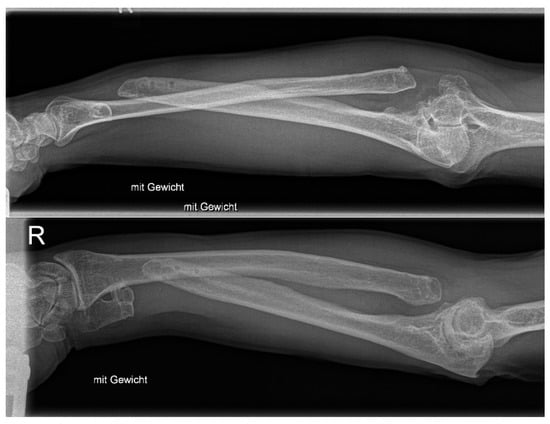

This maneuver improved pronation/supination from 50/0/0° after prosthesis implantation to 90/0/45° at follow-up after a total of two and a half years (initially, it was 10/0/10° before presentation to our department). The mobility in the elbow is currently extension/flexion at 0/0/120°. The patient needed much physiotherapy and training to regain function and finally supinate the arm powerfully due to the retraction of the tendon and the long period of non-use. The DASH score improved from 79 to 42, and grip strength improved from 11 kg to 24 kg two and a half years after implantation. The patient started using the hand again for writing and holding a pen six months after prosthesis implantation. He has returned to playing badminton, which he now does without pain. The mobility of the wrist is currently extension/flexion 60/0/60° and radialduction/ulnarduction 20/0/25°. Finger extension and fist closure are still fully possible. The combined proximal and distal radio-ulnar prosthesis has now been in the forearm for two and a half years. The radiographs show that the prosthesis has healed, and there are no signs of secondary complications, such as stress shielding, loosening, etc. (Figure 4). The patient has almost regained his original life (“I have my old life back”). Of course, we and the patient are still cautious due to the lack of experience, as the options for a revision would open up a whole new chapter.

Figure 4. Follow-up X-ray at 2.5 years after combined proximal and distal DRUJ replacement.